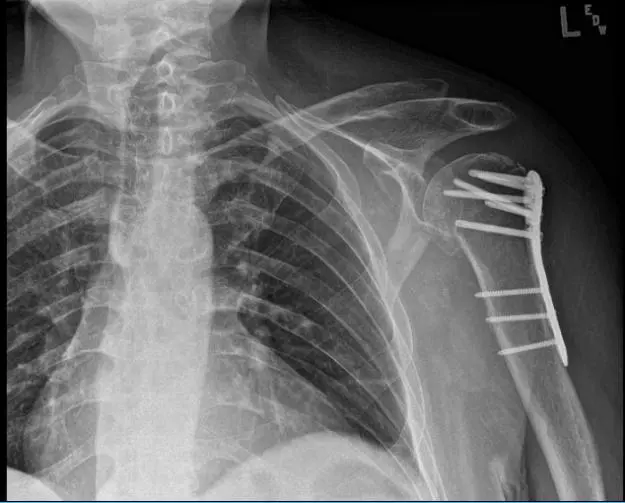

Xray reviewed- found surgically treated comminuted fracture of the humeral head and neck. By this time, we agreed to start Physical therapy.

Post-operative X-ray.

The patient is in status post-surgical repair of a comminuted fracture of the humeral head and neck. Fracture fragments are in good position and alignment. The surgical hardware is intact.